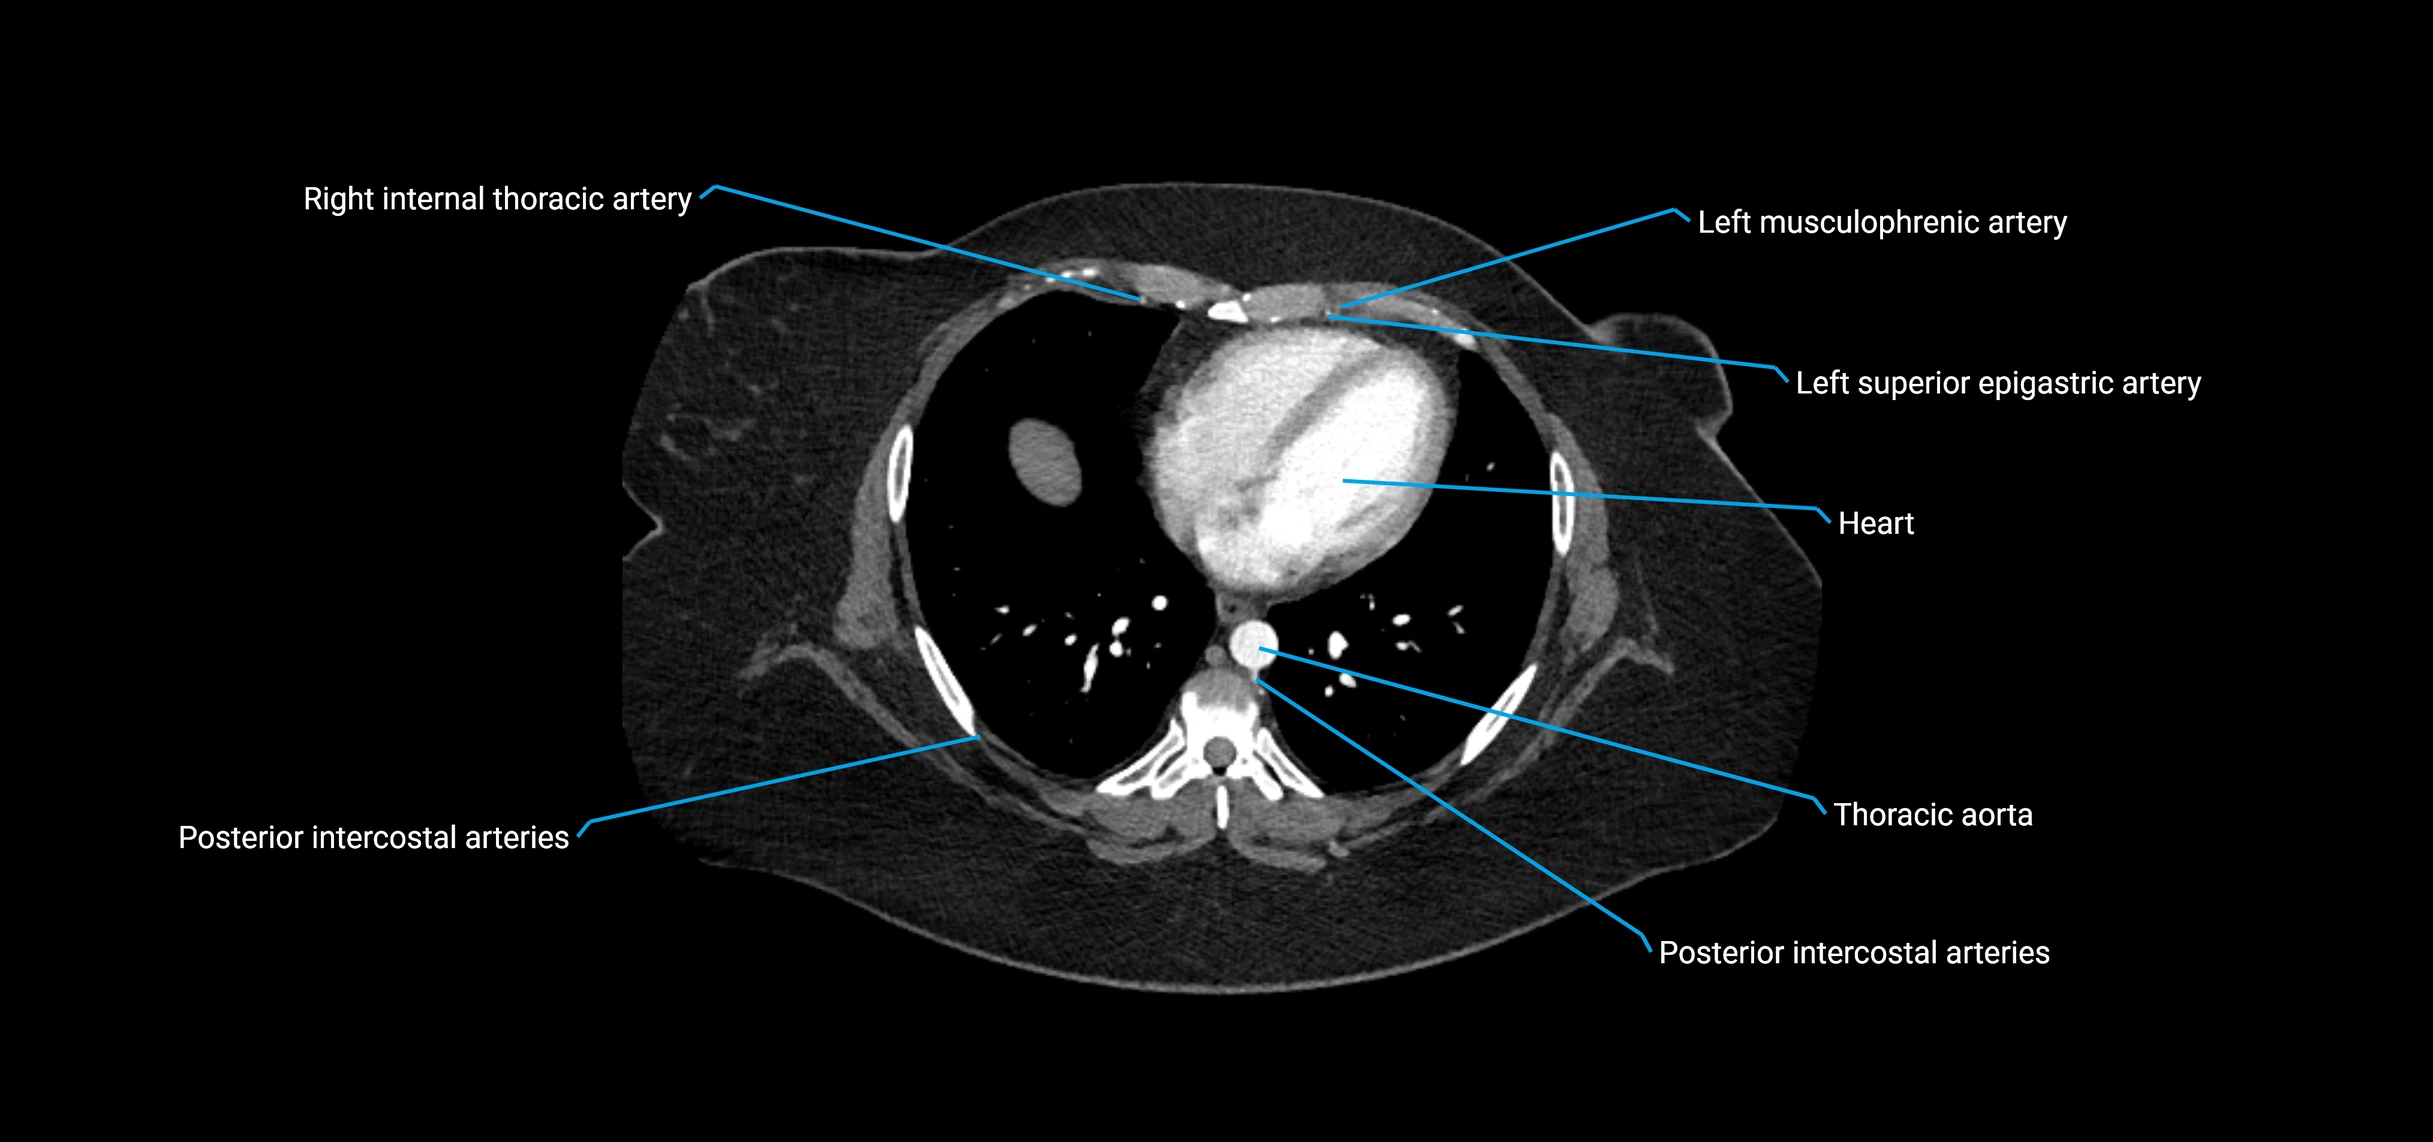

CT Appearance

Non-contrast CT:

• Appears as a tubular soft tissue structure anterior to vertebral bodies

• Calcified atherosclerotic plaques appear as hyperdense foci along the wall

• Useful for screening abdominal aortic aneurysm (AAA) size and mural calcification

Contrast-enhanced CT (CTA):

• Gold standard for abdominal aortic imaging

• Provides excellent detail of lumen, wall, aneurysm, thrombus, and branch vessels

• Multiplanar and 3D reconstructions help in aneurysm measurement, stent graft planning, and dissection evaluation